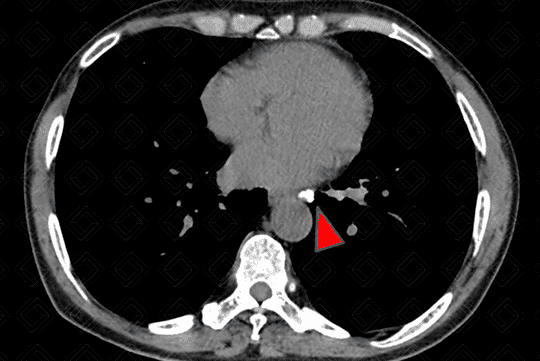

Texto alternativo para a imagem Figura 4 - Créditos: Dra Elazir Mota - Rio de Janeiro/RJ

Na janela de partes moles, as calcificações no interior das opacidades são melhor apreciadas (seta vermelha - figura 3), bem como os linfonodos calcificados no mediastino e hilo pulmonar (cabeça de seta - figura 4).